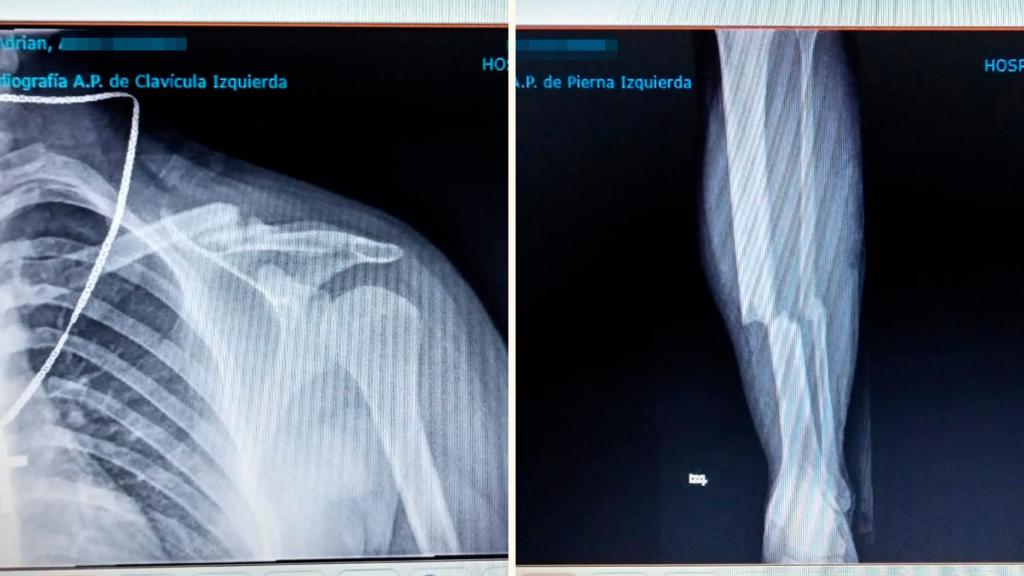

Las radiografías de Adrián con la clavícula rota por tres sitios y la fractura en la tibia y el peroné.

Las radiografías de Adrián con la clavícula rota por tres sitios y la fractura en la tibia y el peroné. Cedida

Tanto es así que mantiene aparcado el sueño de ingresar en el Ejército, debido a que dos años después sigue sin recuperarse de las secuelas físicas que sufrió en el atropello, a bordo de un patín eléctrico. "El Ford me golpeó en el lado izquierdo de mi cuerpo: me partió la tibia y el peroné, me rompió la clavícula en tres partes y en el ojo me pusieron cinco puntos porque me lo rajó de la ceja al lagrimal", detalla Adrián, para el que no ha terminado el calvario con el bisturí, ya que tendrá que pasar por tercera vez por la mesa de operaciones, por una placa de hierro que tiene en su brazo.

- Adrián Ocaña García: El cirujano que me operó, me dijo que para hacerme las lesiones que tenía el conductor iría circulando a 90 kilómetros por hora por una zona que está limitada a 20 kilómetros. En la primera operación, permanecí once horas en el quirófano para que me arreglasen la pierna, y en la segunda, me sacaron hueso de la cadera para injertarlo en mi clavícula. También me pusieron placas y ocho tornillos.